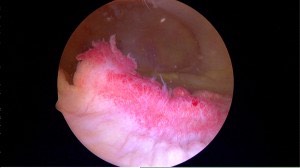

Inflammed Knee Synovium

Inflammed syovial lining found in arthritis